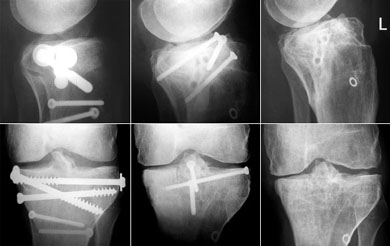

Der Röntgencheck in Chur brachte eine besorgniserregende Erkenntnis: Die Schmerzen am unteren Patellarand könnten von einer bereits beginnenden Arthrose herrühren (siehe weiter unten). Ansonsten hab ich wieder eine Lizenz zum Skifahren - und die Gewissheit, dass ich keine grössere Schwellung mehr im Knie habe. Und immerhin bin ich vom Metall befreit... ausser dem "Heiligenschein" rechts unten, einer eingewachsenen Unterlagsscheibe, die immerhin dereinst Angestellte eines Bestattungsunternehmens beschäftigen wird: "Wie finden wir das kleine Ding, das in dieser Urne so klimpert?" - Die folgende Bilderserie zeigt der Verlauf von den Schrauben der ersten OP über diejenigen der Korrekturosteotomie vom April 2002 bis zum Dezember 2002.

Sie können auf die einzelnen Bildfragmente klicken, um eine grössere Fassung des Ausschnittes zu sehen.

Sorgen macht die Kniescheibe: Auf der folgenden Bilderserie von Mai 2001 bis Dezember 2002 (aufs Bild klicken für Originalgrösse!) ist deutlich sichtbar, wie sich am linken unteren Patellarand ein kleiner Höcker gegen das Wadenbein hin bildet. Dieser Auswuchs (Osteophyt) könnte der Grund für den noch vorhandenen Hauptschmerz sein; er könnte auch vom Bechterew herrühren oder durch diese Krankheit zumindest verstärkt worden sein.

Ebenfalls gut zu sehen ist jedoch die schöne Heilung der ursprünglichen Bruchstelle (links unten im Bild) - einen Monat nach der Operation (links) klafft noch eine deutliche Lücke, die im Lauf der Zeit von neuer Knochenstruktur überwachsen wird.